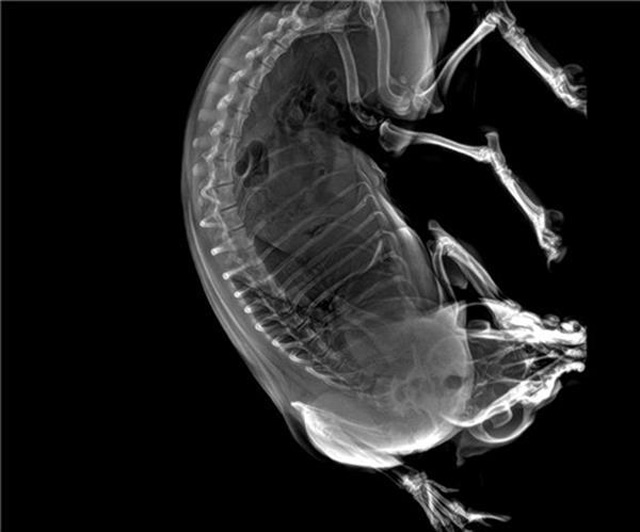

寵物DR數字成像實現全數字化和無膠片化鋪平了道路

寵物DR的工作原理是X光線穿透動物體後在屏幕或者膠片上麵顯示體內影像。輔助寵物醫生讀片跟準確的治療,寵物DR顯示是寵物醫院診所的配置,提高了診斷的效率。DR的檢測效率比X線高44%,成像快采集時間10MS以下。3秒左右就可以看到檢查圖像。常規的胸部DR還要幾分鍾。所以寵物DR的出片速度是非常快的。很高的空間分辨率低噪音。可以獲得高清圖像,提高檢測正確率避免誤診等等問題。數字化圖像的優勢是可以保留原始數據,圖片識別,二三維的重建,醫學影像學實現全數字化和無膠片化鋪平了道路。提供照片打印服務,防止照片丟失而重複照片。有針對性的對圖像進行處理,以提高診斷率。寵物DR的輻射量很低的,對人體的輻射風險不大。